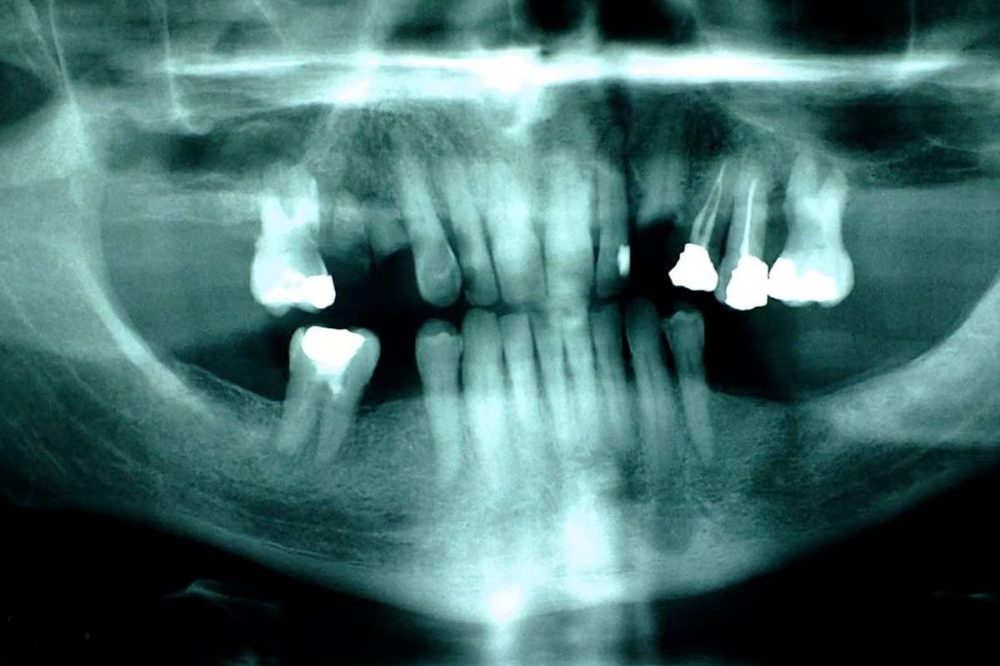

اتجاه «ثوري» لعلاج تسوس الأسنان بالخلايا الجذعية

وتُشير «The Economist»، إلى أن 2.5 مليار إنسان في العالم يعانون من تسوس الأسنان، لذلك قد يصبح اكتشاف علماء جامعة واشنطن أفضل بديل لعملية حشو الأسنان المزعجة.